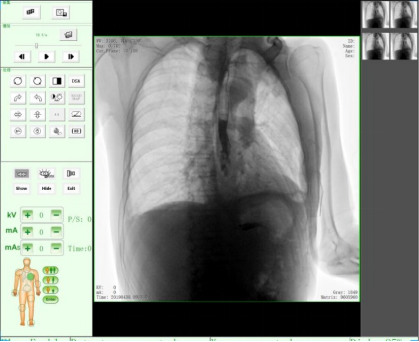

三、醫(yī)學(xué)用途,醫(yī)用X射線機作為醫(yī)學(xué)診斷重要的設(shè)備之一,目前市面上醫(yī)用X射線機種類主要有DR、CR、C形臂、乳腺機、胃腸機、口腔CBCT等醫(yī)療器械。設(shè)備依據(jù)X射線的穿透作用、差別吸收、感光作用和熒光作用,利用人體各組織的密度和厚度不同,通過檢測圖像陰影濃淡的對比,結(jié)合臨床表現(xiàn)、化驗結(jié)果和病理診斷,即可判斷人體某一部位/內(nèi)部器官是否正常。此類X光機廣泛應(yīng)用于醫(yī)療機構(gòu)與場所,為相關(guān)單位提供了快速的醫(yī)療診斷。